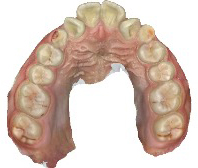

before

after

患者さんの年齢 20代 女性 症状 ガタガタを治したい 治療内容 マウスピース矯正治療 費用 90万(税抜) 治療期間・回数 治療期間2年、通院回数10回 メリット 笑顔が綺麗 デメリット・リスク 期間がかかることがある - マウスピース矯正